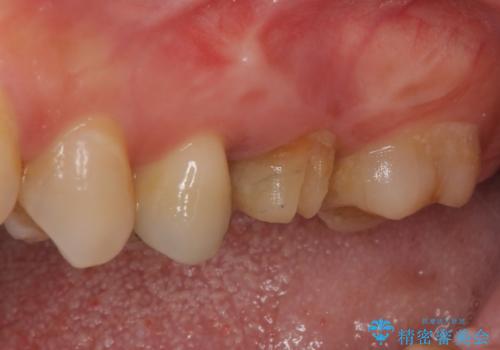

割れてしまった奥歯 インプラント治療

- 近医にて抜歯が必要と診断されたとのことで来院された患者様です。

術前の診査では、歯が破折している可能性が高いものの、確実に抜歯が必要と診断ができない状態でした。

状況次第では抜歯が必要となり、その際にはインプラント治療を行うことを了承いただいた上で、破折していない場合には根管治療を行うこととしました。

土台の材料を外して顕微鏡下で確認したところ、歯根にまで及ぶ破折が認められたため、インプラント治療を行うこととしました。